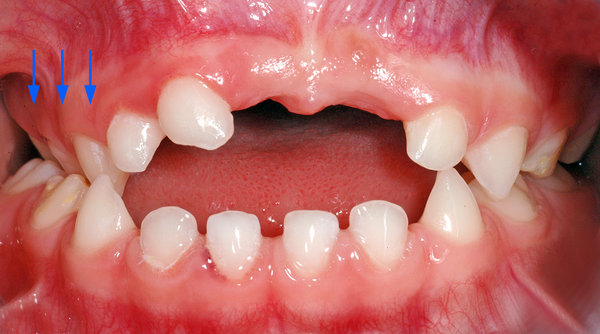

- Kreuzbiss im Seitenzahnbereich auf der rechten Seite (blaue Pfeile im Bild).

- Offener Biss in der Front (das heisst, dass die Schneidezähne beim Zusammenbeissen nicht «übereinander» oder aneinander kommen; ist im Bild blau markiert).

- Kreuzbiss rechts (blaue Pfeile)

- Offener Biss in der Front (blau markierte Zone)